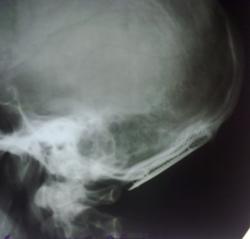

Необычный череп.

Сегодня сделали краниограммы пациенту.

Знаю такие сеточки ставят нейрохирурги,выполняя пластику,только вот дефекта костей свода не вижу.Хотелось узнать анамнез.

Прооперирован по поводу сосудистой мальформации в области мозжечка в январе 2011 года.